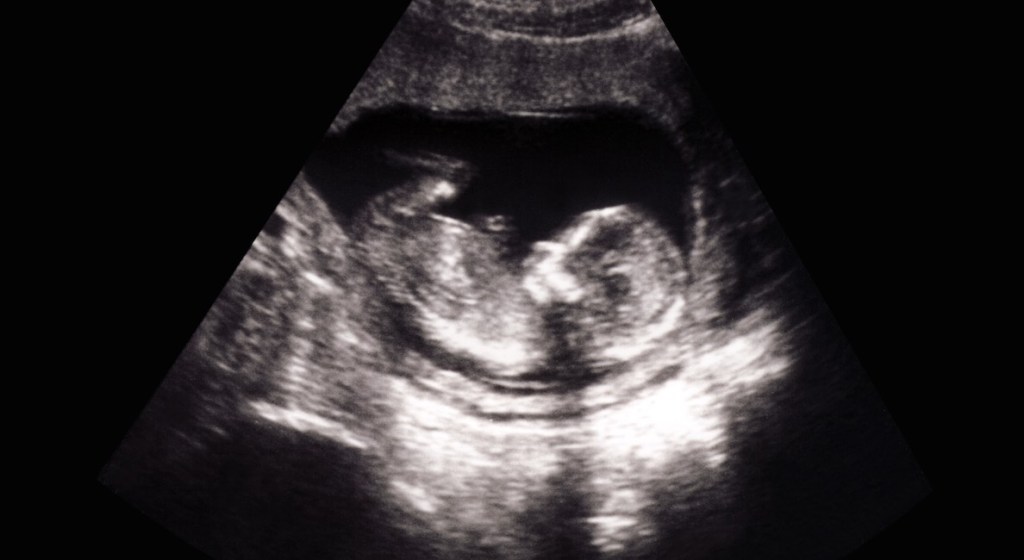

All’inizio del 2022, il New York Times ha finalmente riportato ciò che Live Action News documenta da anni: il fatto cioè che l’analisi del sangue prenatale non è accurata e non dovrebbe essere utilizzata come strumento diagnostico. Alcuni test di screening prenatale non invasivi (test NIPT o NIPS) per la rilevazione di particolari condizioni genetiche procurano falsi positivi fino al 93% delle volte, ma sono spesso usati per spingere i genitori ad abortire. Ora la Food and Drug Administration (FDA) statunitense avverte i genitori e gli operatori sanitari che nessun test NIPS è stato approvato dalla FDA.

La FDA osserva che dovrebbero essere effettuati ulteriori test per confermare una diagnosi, ma è consapevole che molti pazienti hanno preso “decisioni sanitarie critiche” – ovvero l’aborto – sulla base dei soli risultati dei test di screening. “In particolare, le donne incinte hanno interrotto la gravidanza basandosi solo sui risultati dei test NIPS”, ha affermato la FDA. “Senza un test diagnostico che confermi i risultati, non c’è modo di sapere se il feto abbia effettivamente l’anomalia genetica segnalata dal test di screening”.

Secondo uno studio del 2014, il 6% dei bambini con un esito “positivo” del test di screening per una determinata anomalia è stato abortito senza che i genitori si fossero sottoposti a un test per confermare la diagnosi, come un’amniocentesi. In Irlanda, sulla base dei risultati dei test NIPS che avevano identificato una possibile anomalia genetica nel figlio, una coppia ha ricorso all’aborto. Solo dopo che avevano già ucciso il loro bambino, un altro risultato del test ha indicato che era sano.